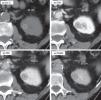

Se presenta como un tumor periférico circunscrito (pequeño y homogéneamente sólido o mayor quístico-hemorrágico) o como una lesión infiltrante e invasora de venas, con peor pronóstico.

Por su baja densidad vascular, el realce es menor que en otras neoplasias renales, lo que facilita su caracterización. En tomografía computarizada puede no realzar de manera concluyente, y entonces es indistinguible de un quiste hiperatenuante. La ecografía con contraste y la resonancia magnética son más sensibles para detectar vascularización. Son además característicos un patrón vascular específico, hipointensidad en T2, restricción de la difusión del agua y aumento de señal en fase opuesta.

It presents as a circumscribed peripheral tumor (small and homogeneously solid or larger and cystic/hemorrhagic) or as an infiltrating lesion that invades the veins, which has a worse prognosis.

Due to their low vascular density, papillary renal cell carcinomas enhance less than other renal tumors, and this facilitates their characterization. On computed tomography, they might not enhance conclusively, and in these cases they are impossible to distinguish from hyperattenuating cysts. Contrast-enhanced ultrasonography and magnetic resonance imaging are more sensitive for detecting vascularization. Other characteristics include a specific vascular pattern, hypointensity on T2-weighted images, restricted water diffusion, and increased signal intensity in opposed phase images.